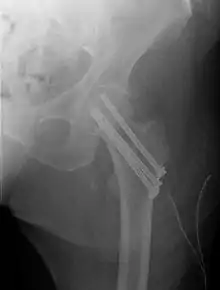

Fracture treated with cannulated screws

For low-grade fractures (Garden types 1 and 2), standard treatment is fixation of the fracture in situ with screws or a sliding screw/plate device. This treatment can also be offered for displaced fractures after the fracture has been reduced.

Fractures managed by closed reduction can possibly be treated by percutaneously inserted screws.[37]